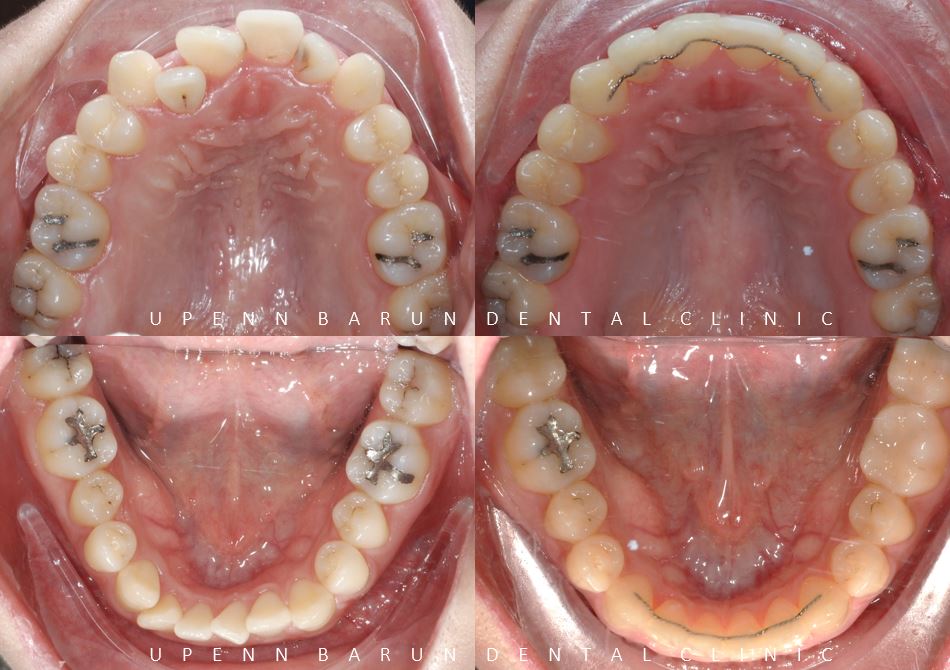

앞니 충치치료와 , 어금니 충치치료 후 교정치료가 완료된 사진입니다

악궁 확장 기능에 탁월한 데이몬 클리어 교정장치를 통해

발치를 하지 않고 비발치교정으로 약 1년 8개월의 기간동안 진행 해드렸습니다 ^^

위, 아래 앞니가 정확히 맞물리지 않았던 이전과는 달리

입천장쪽으로 쏙 들어가 있던 위앞니가 제 자리를 찾으며

치아들이 가지런히 펴졌는데요 ^^